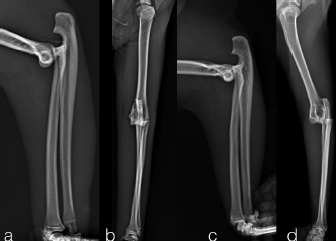

The case 1 and case 2 were evaluated every 5 days until the final evaluation at 22 and 18 days after surgery, respectively. The implants were well tolerated with acceptable three legs gait in both cats. The owners reported no management’s concern of the patient at home. At the final control, the stabilization bars were removed after clinical and radiographic evidence of joint reduction and stability. The Kirschner wires were left for further 5 days later, to be useful in case of reluxation. Protective caps and bandage were applied on the tips of Kirschner wires until their removal. Dermatitis around the pin tracts was the only minor complications associated with the transarticular external skeletal fixation, resolved after implants removal. Thirty days after surgery, in both cases, the clinical examination showed a grade 3/4° lameness (Brunnenberg, 2001), a limited range of motion (150°/70°) and a painless manipulation with no swelling visible. Mild osteoarthrosis was present at radiographic control. For both cats, physiotherapy sessions was not require; however, the owners did some home exercises like gentle passive motions, while restricted movement was continued for another 3 weeks. At 8 weeks after reduction, the cats were no longer lame and the exercise was well tolerated. The range of motion was mildly reduced without pain or joint crepitation. The radiographic follow-up at 2 months after reduction showed mild evidence of osteoarthritis (Fig. 3). The long term follow-up at 3 years assessed with a clinical examination, in both patients, showed normal function and good quality of life despite the mild reduction of the range of motion and moderate development of elbow osteoarthrisis (Fig. 4).

Fig. 3. The radiographic follow-up at two months after reduction showed mild radiographic evidence of osteoarthritis. In the cranio-caudal view (b), near the lateral epicondyle, we can notice a small chip fragment (case 1).